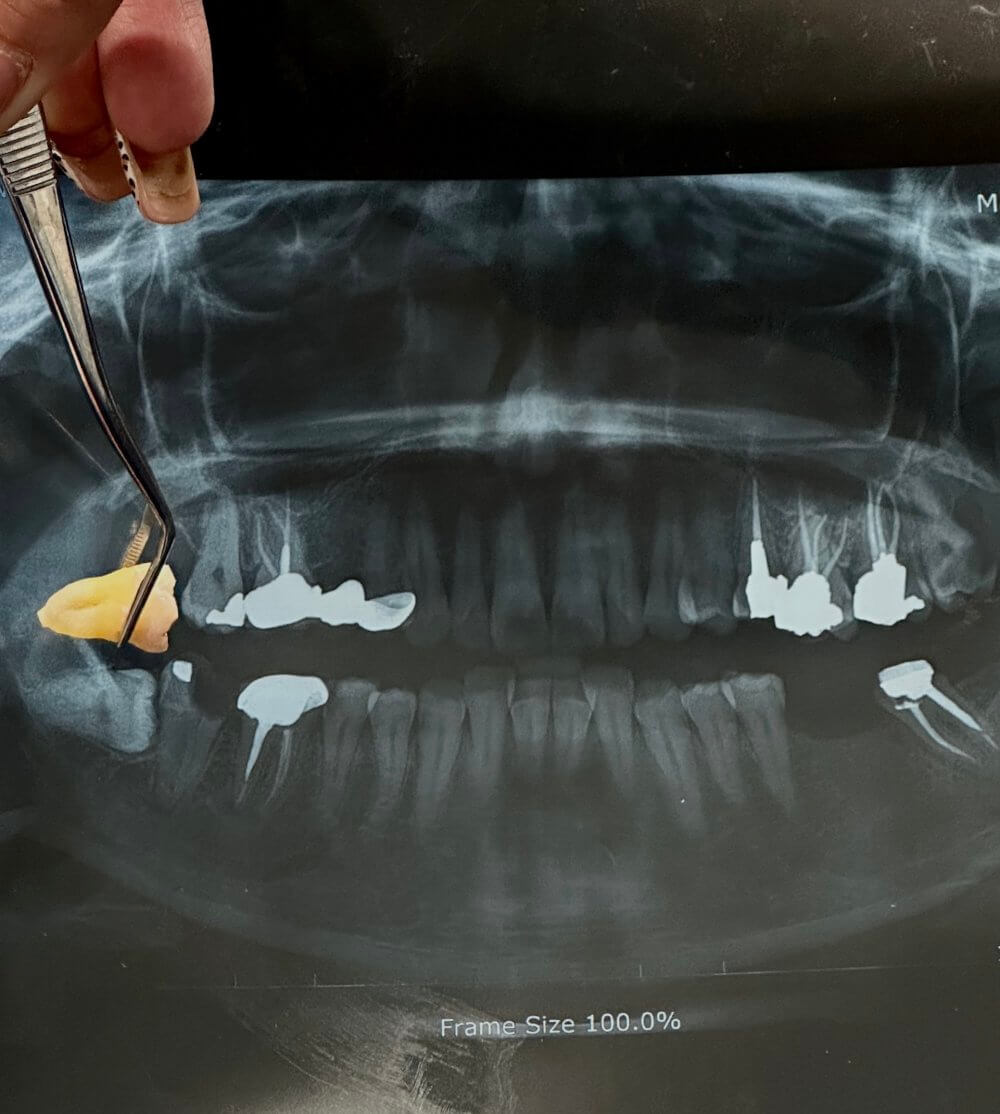

درمان‌های جراحی و تخصصی بعضی مشکلات دندان و لثه نیازمند درمان‌های پیشرفته‌تر هستند. جراحی و کشیدن دندان، خارج کردن دندان‌های آسیب‌دیده یا نهفته با کمترین میزان آسیب است.

Tooth-Extraction-02 Tooth-Extraction-02